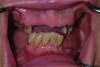

Pre-treatment smile of patient with terminal dentition.

Figure 17

The patient’s intraoral condition.

Figure 18